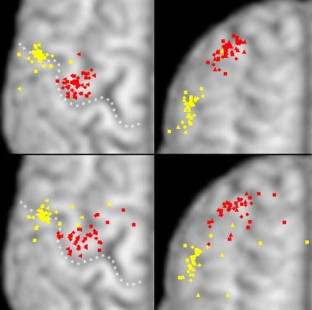

Fig. 1

Fig. 2